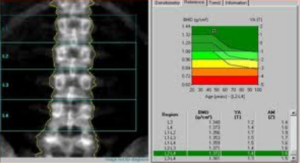

Vertebral Fracture Assessment (VFA/MXA)

La VFA viene eseguita utilizzando la tecnologia Dual-energy X-ray Absorptiometry (DEXA), la stessa impiegata per la misurazione della densità ossea. Questa tecnica ha guadagnato rapidamente terreno nella pratica clinica grazie alla sua praticità e sicurezza. Molti sistemi moderni utilizzano una tecnologia a raggio a ventaglio (fan-beam) con un braccio rotante che acquisisce l’immagine laterale del paziente in posizione supina, eliminando gran parte delle distorsioni geometriche tipiche della radiologia conica.6

I vantaggi della VFA rispetto alla MRX includono:

- convenienza diagnostica: consente di valutare BMD, TBS e morfometria in un’unica sessione, fornendo un quadro clinico immediato;

- ridotta esposizione alle radiazioni: utilizza dosi di radiazioni significativamente inferiori, rendendola adatta per monitoraggi frequenti;

- posizionamento semplificato: il paziente rimane supino, il che è spesso più confortevole per soggetti anziani o con dolore acuto rispetto alla posizione eretta o laterale richiesta per la radiografia tradizionale.